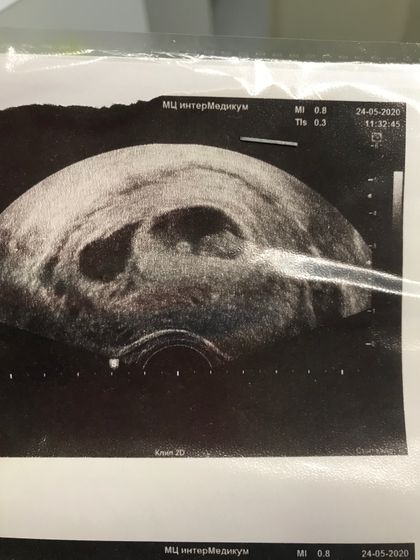

Здравствуйте, девочки. Такой вопрос. Была на узи. Срок 7,5. Поставили под вопросом второе пя или гематому. Одно пя с эмбрионом 32мм. Второе 20х15мм. Было у кого-нибудь так? Появился потом эмбриончик? уже извелась вся.

Я поняла, но во втором пока совсем пусто. И жт одно. Но я знаю, что и одно бывает жт с такой двойней. Плюс второе пя на срок 6-7 недель. Понимаю что жм должно быть видно, но буду надеяться на лучшее. Потому что у меня даже живот не тянет как с дочкой. С дочкой была гематома и выглядела по другому